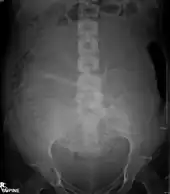

Projectional radiographs

Projectional radiography is the practice of producing two-dimensional images using X-ray radiation. Bones contain a high concentration of calcium, which, due to its relatively high atomic number, absorbs X-rays efficiently. This reduces the amount of X-rays reaching the detector in the shadow of the bones, making them clearly visible on the radiograph. The lungs and trapped gas also show up clearly because of lower absorption compared to tissue, while differences between tissue types are harder to see.

Projectional radiographs are useful in the detection of pathology of the skeletal system as well as for detecting some disease processes in soft tissue. Some notable examples are the very common chest X-ray, which can be used to identify lung diseases such as pneumonia, lung cancer, or pulmonary edema, and the abdominal x-ray, which can detect bowel (or intestinal) obstruction, free air (from visceral perforations), and free fluid (in ascites). X-rays may also be used to detect pathology such as gallstones (which are rarely radiopaque) or kidney stones which are often (but not always) visible. Traditional plain X-rays are less useful in the imaging of soft tissues such as the brain or muscle. One area where projectional radiographs are used extensively is in evaluating how an orthopedic implant, such as a knee, hip or shoulder replacement, is situated in the body with respect to the surrounding bone. This can be assessed in two dimensions from plain radiographs, or it can be assessed in three dimensions if a technique called '2D to 3D registration' is used. This technique purportedly negates projection errors associated with evaluating implant position from plain radiographs.[101]